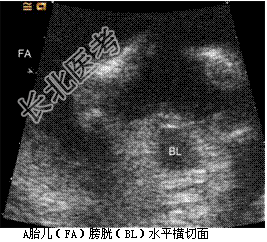

- [材料题] 孕妇,30岁,孕2产0孕22周。超声(孕12周):宫内妊娠,单绒毛膜囊双羊膜囊双活胎,A胎儿NT0.32cm,B胎儿NT0.12cm。孕22周复查超声如下图。

- 简答题1、根据上述声像图,试描述。